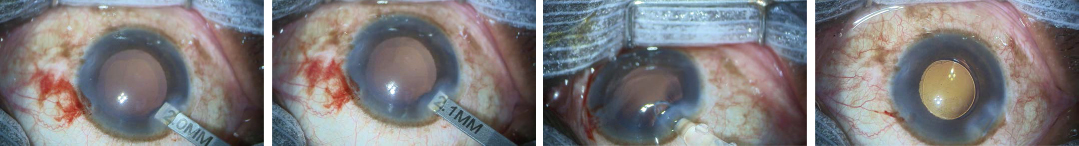

ONE Step Preloaded IOL

Primus-HDⓇ

1.8 ~ 2.2mm incision

2.2mm Incision으로 매우 충분합니다.

Implantation of the Primus-HD via an incision size of 2.0 mm into the bag